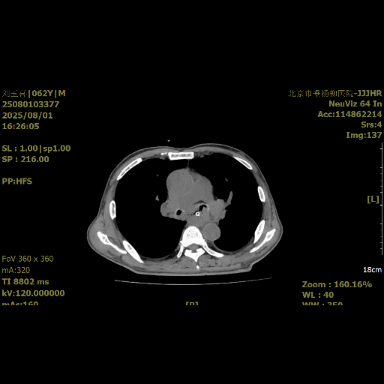

图1术前影像

近日,清华大学附属垂杨柳医院胸外科接诊一位确诊为食管气管瘘的中年男性患者。其20日前出现吞咽困难,1周前突发不明原因发热伴频繁咳嗽、咳痰,体温最高达38.5℃。外院行胸部增强CT检查,提示食管占位合并食管气管瘘。